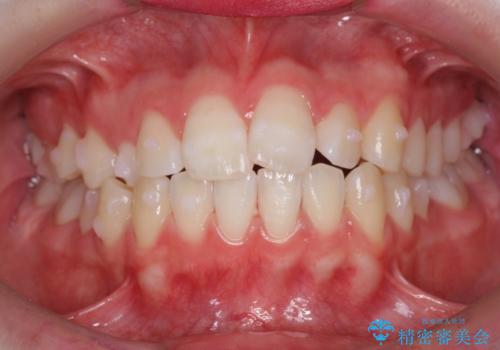

前歯のがたつき 乳歯を抜かずに矯正

- 前歯のがたつきを主訴に来院。

右上に乳歯が残っていましたが、後継永久歯がないため、抜かずに矯正しました。

乳歯の部分が反対咬合でしたが、歯列矯正で被蓋が改善するように移動させました。

右上の乳歯は移動させましたが、幸い矯正後にぐらつくこともなく、そのまま抜けるまで使うことにしました。